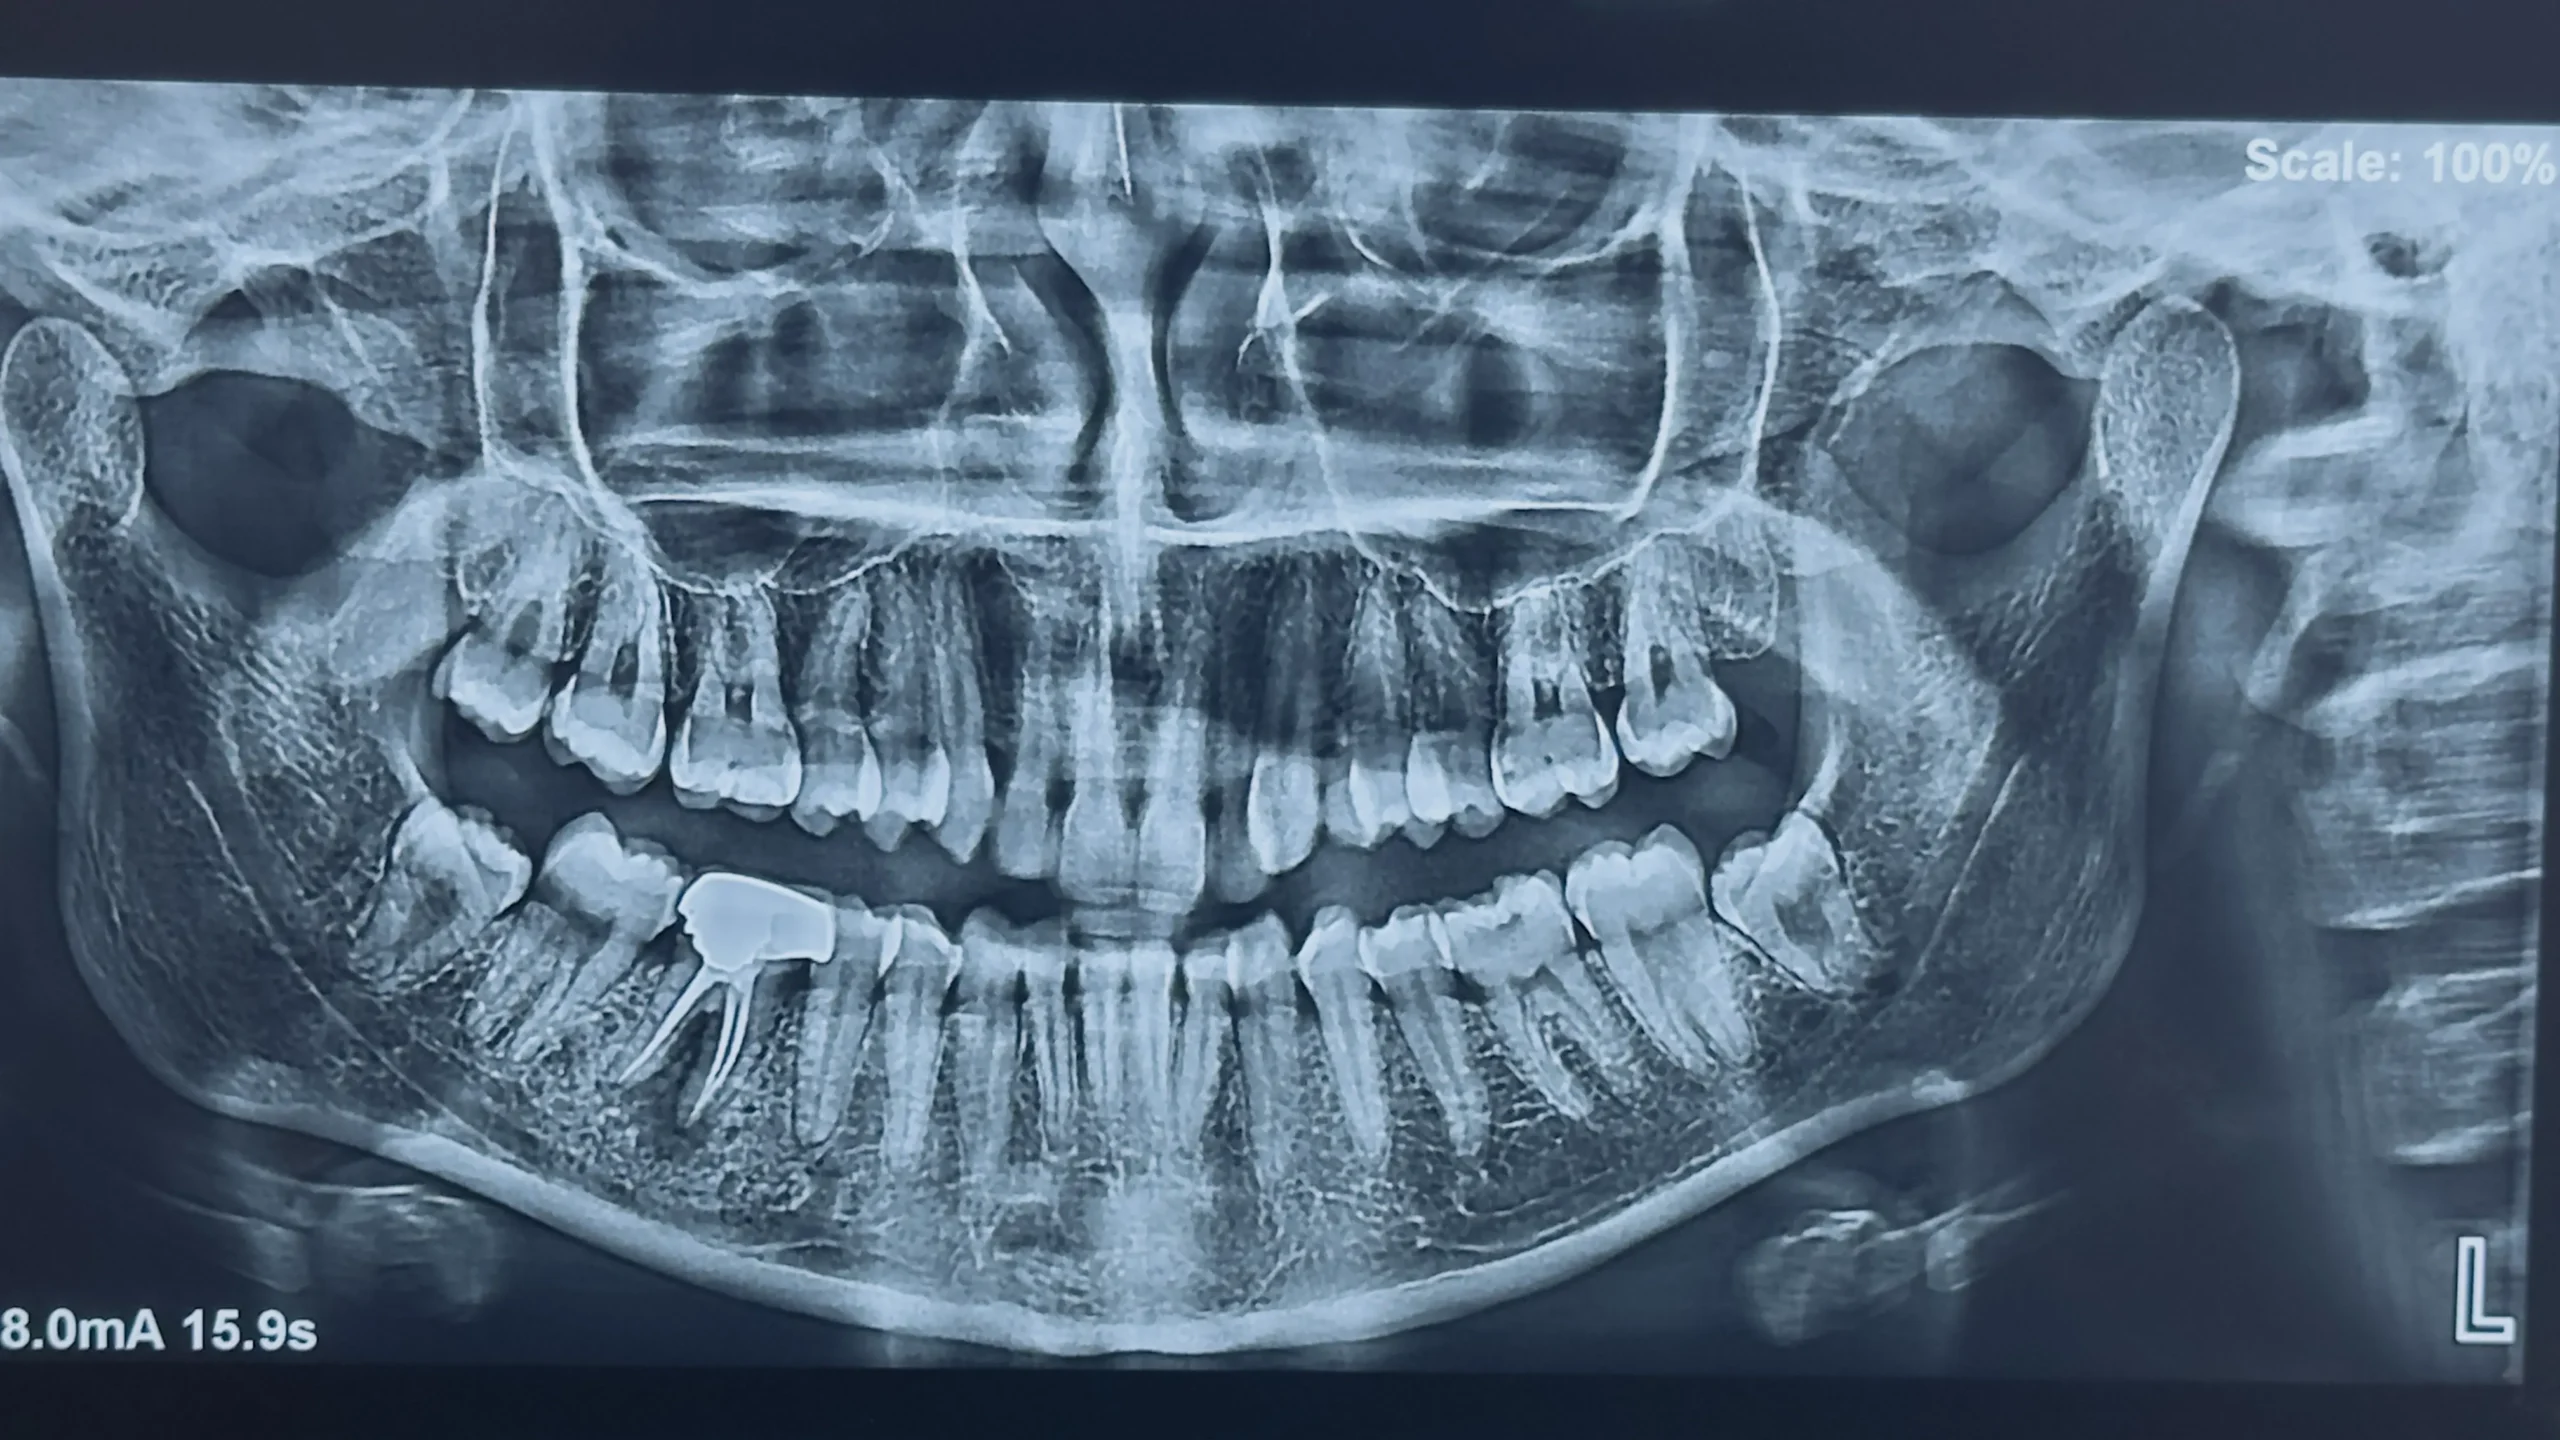

Step 1: Initial Consultation

- Oral examination

- X-rays

- Treatment planning

- Cost estimate

- Severity of the Dental Case

- Duration of Treatment